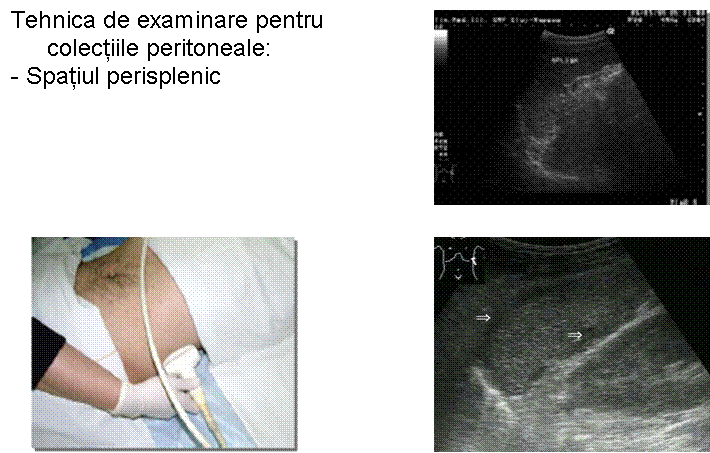

TRAUMATISM ABDOMINAL EXAMINARE FAST

Trusa de lavaj peritoneal Ruptura

de splina

Aspect postsplenectomie Hematom subcapsular

splenic rupt